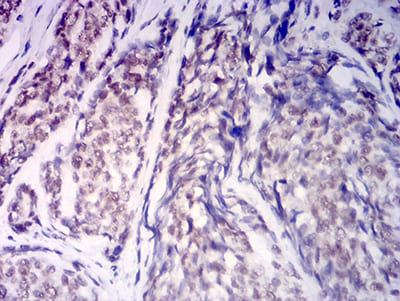

Immunohistochemical analysis of paraffin-embedded human cervical cancer tissues using KDM1A mouse mAb with DAB staining.

Immunohistochemical analysis of paraffin-embedded human esophageal cancer tissues using KDM1A mouse mAb with DAB staining.